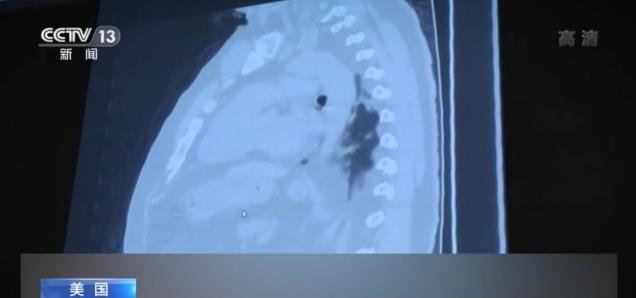

今年6月,由于新冠肺炎住院患者太多,得克薩斯州休斯敦聯(lián)合紀(jì)念醫(yī)療中心將兩個(gè)普通病區(qū)改造為新冠肺炎隔離病區(qū),而現(xiàn)在,由于患者人數(shù)激增,醫(yī)院不得不再增加一個(gè)隔離病區(qū)。